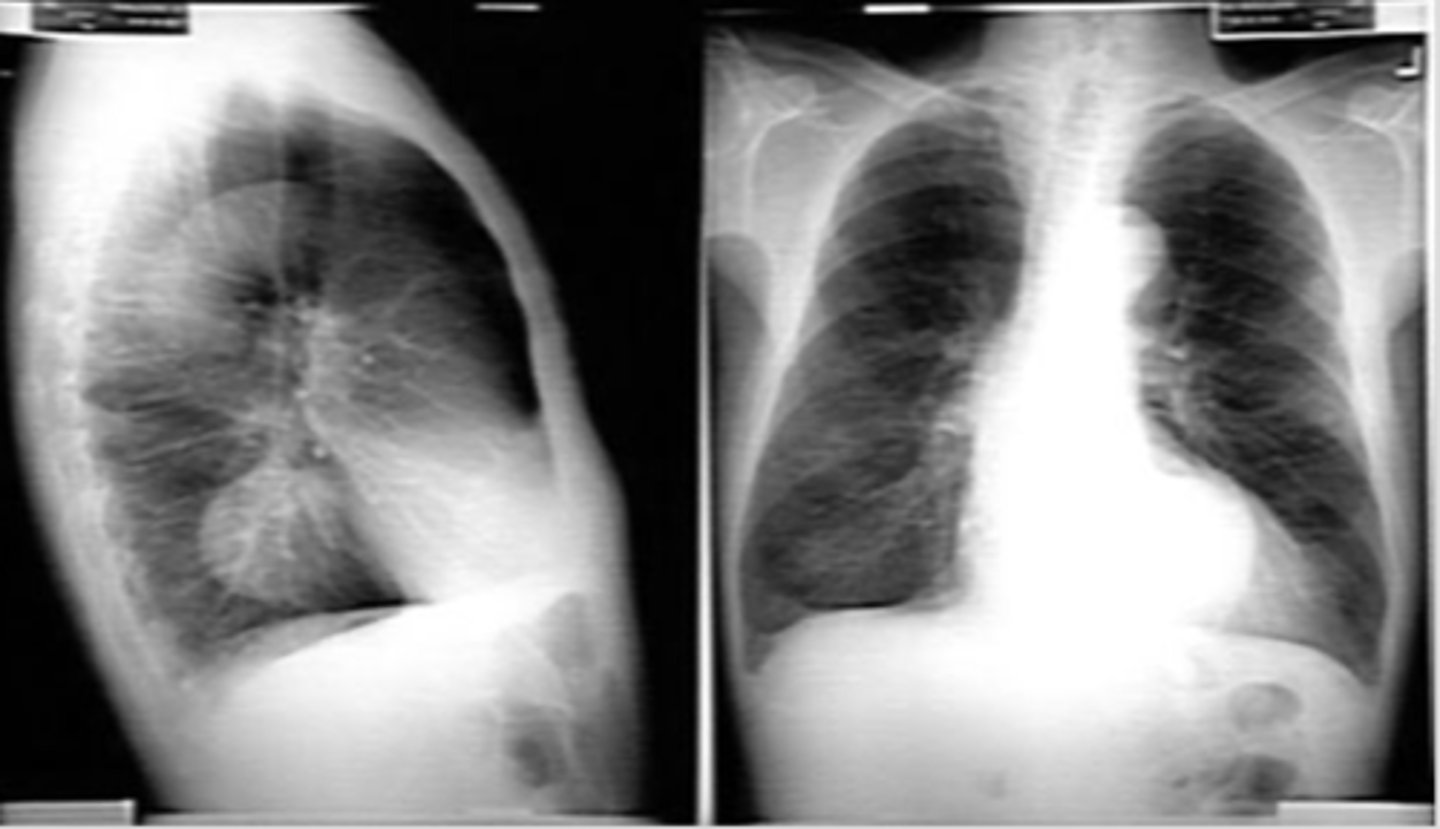

Pneumothorax (caused by stabbing)

visceral pleural line in the left chest (white arrows).

horizontal line along the base of the left hemithorax, which represents an air-fluid level (black arrows), showing that the patient has a hemopneumothorax.

2 key findings in this x-ray and dx

<p>2 key findings in this x-ray and dx</p>